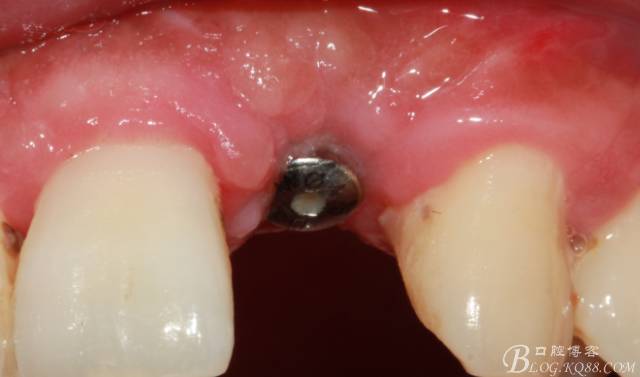

術(shù)后1個月

術(shù)后5個月